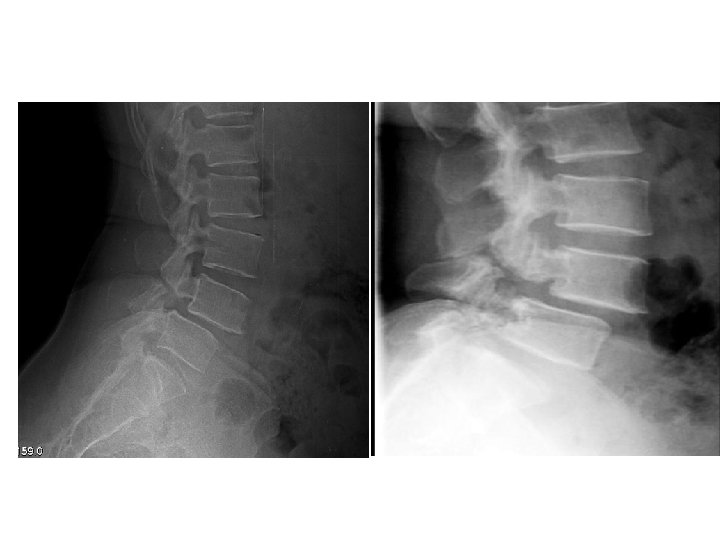

• Imaging studies : - X-ray : AP radiographic findings are usually normal in spondylolysis. The oblique views ( Rt. And Lt ) are particularly screened for the "Scotty dog" lesion in the pars interarticularis. The pars defect is represented by the collar on the Scotty dog. - ( 99 m Tc) / SPECT bone scan : superior to CT/MRI : these scans can aid in establishing the acuity of the lesion or in identifying the site of the problem in an athlete with negative plain radiography results but whose clinical course is suggestive of a pars interarticularis fracture.

• Imaging : - X-ray : AP , lateral , oblique * on lateral view : forward slip is evident. * on oblique view : gap in pars interarticularis. - MRI : to evaluate impingement of neural elements. - CT : for bony pathology. - CT myelogram : when MRI contraindicated.